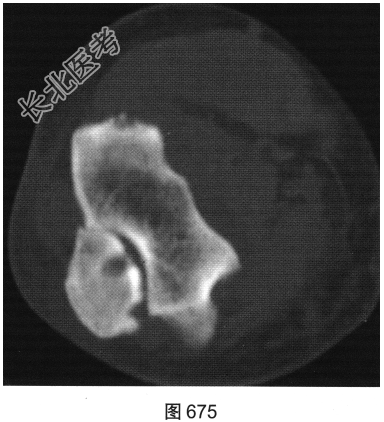

- [材料题] 患者女性,62岁,右侧肘关节肿胀、疼痛1年余。肘关节正侧位X线片及CT检查见图673~图676。

- 简答题1、请对该患者影像征象进行描述。

- 简答题2、根据题干中患者的临床表现及影像特征,请问该患者应首先考虑哪种疾病?